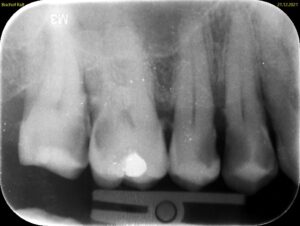

Die Aufnahme dauert nur Sekundenbruchteile. Da der Sensor nah am Zahn liegt und der Röntgenstrahl gezielt auf einen kleinen Bereich gerichtet ist, liefert der Zahnfilm eine deutlich höhere Detailschärfe als das OPG (Orthopantomogramm). Feine Strukturen wie beginnende Karies, Wurzelkanäle oder der exakte Verlauf des Knochens an einzelnen Zähnen lassen sich präziser beurteilen.

Typische Einsatzgebiete sind die Kariesdiagnostik (besonders die sogenannten Bissflügelaufnahmen für die Zahnzwischenräume),

Die Beurteilung von Wurzelkanalfüllungen, der Verdacht auf Wurzelspitzenentzündungen, die Kontrolle nach Zahnentfernungen oder Implantationen sowie die genaue Darstellung des Knochenabbaus bei Parodontitis. Ein vollständiger Röntgenstatus aus 10 bis 14 Zahnfilmen zeigt das gesamte Gebiss in hoher Auflösung, wird aber wegen des höheren Aufwands nicht routinemäßig angefertigt.